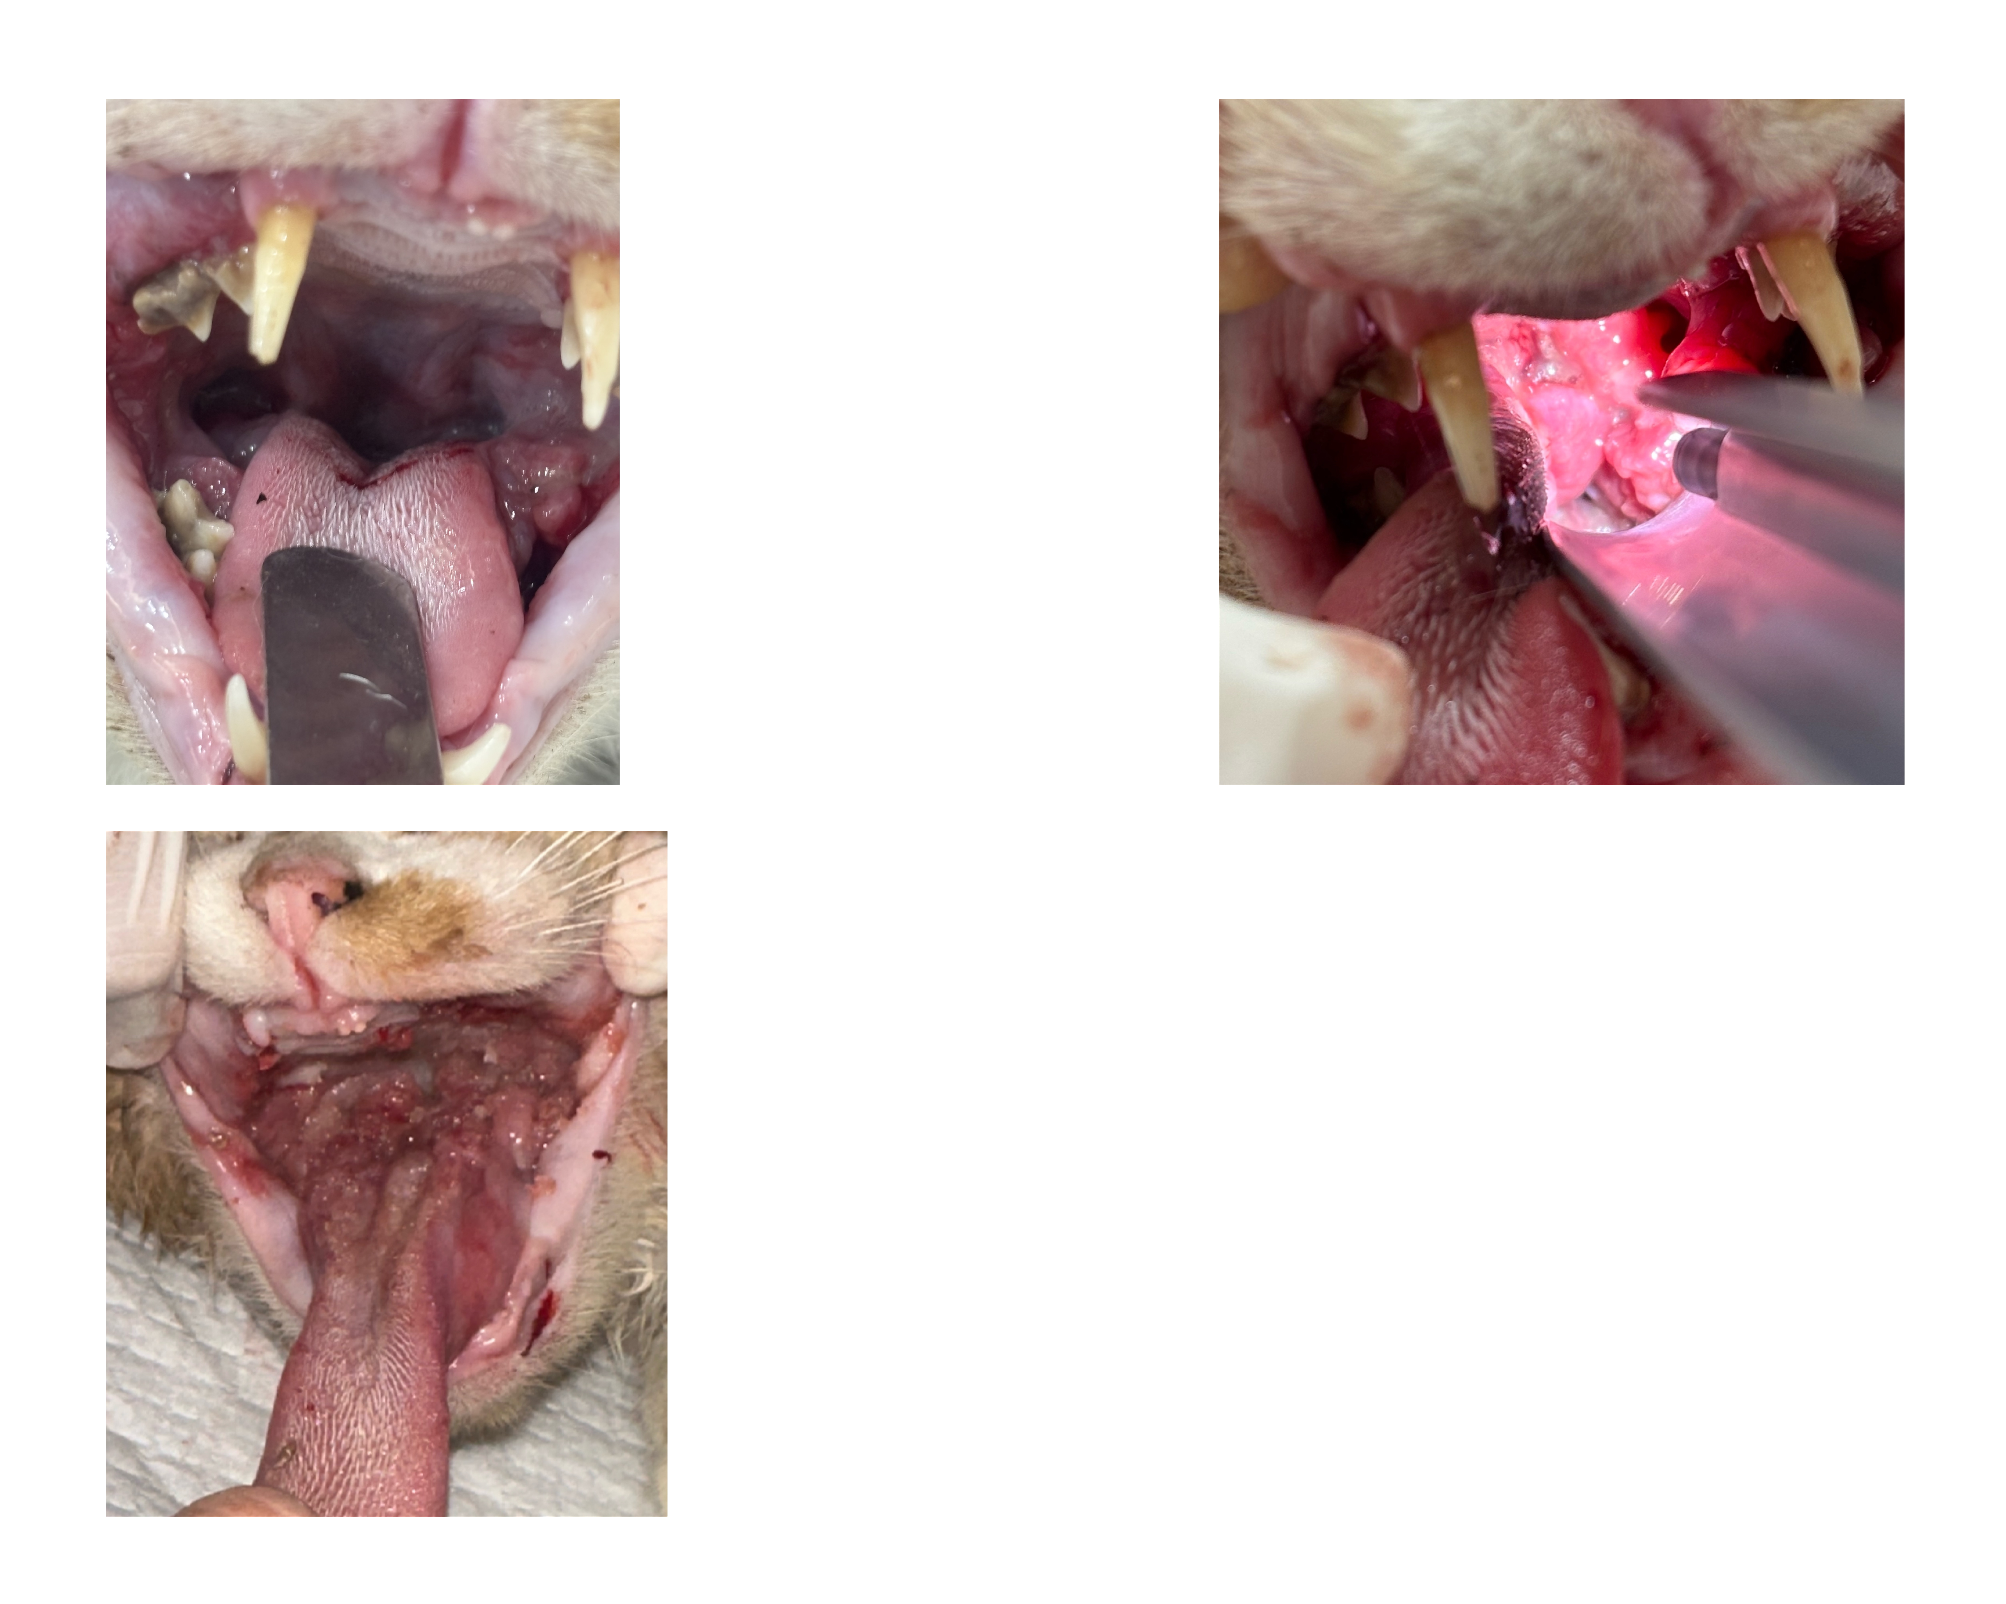

| 치료전 대상묘 사진 |   |

| 치료과정 | 호빵이는 저녁에도 습식을 먹으러 매일 나오지는 않던 녀석이라 구조가 걱정이었습니다. 습식 시간에 나타나길 기다리다가 한 차례 구조에 실패해 마음을 졸이게 했지만, 겨울집이나 여름집을 마련해 두는 곳에는 잘 머무르곤 했기에 이튿날인 10월 21일(화) 낮에 급식소와 집을 마련해 둔 곳 근처에 포획틀을 설치했고 무사히 구조할 수 있었습니다. 미리 연락해 둔 병원으로 곧바로 이동하였고, 사납고 사람 손을 타지 않는 성격인 터라 마취한 후 대기 시간을 가진 후 본격적인 검사에 들어갔습니다. 이 병원에서는 마취 후 상태를 보고 발치가 필요한지 아닌지를 판단한다고 하였는데요, 호빵이는 오랫동안 구내염을 앓아 왔기에 전발치가 필요한 상태임을 진단받았습니다. 그렇게 당일 모든 이빨에 대한 전발치를 진행하였고, 특히 목 안쪽에 염증이 심했던 상태라 조금 편하게 호흡을 할 수 있도록 추가적인 처치를 해 주셨다고 했습니다. 또 2주 동안 효과가 지속되는 항생제 처치도 진행하였습니다. 불행 중 다행히도 혈액 검사 결과 별다른 문제는 더 발견되지 않았습니다. 병원 방침상 발치 후 당일 퇴원한다고 하였으나, 힘든 수술을 한 아이를 바로 방사할 수는 없어 하루 동안 입원을 부탁드렸고 다음 날인 10월 22일(수) 오전에 호빵이를 데려와 원래 지내던 곳에 제자리 방사하였습니다. |

| 대상묘 치료중 사진 |     |

앗 중간에 올린 사진들이 다 첨부가 안 된 것 같네요..ㅠㅠ

치료 전 대상묘 사진 / 대상묘 치료중 사진 / 치료 완료 후 사진 다시 올려 봅니다!

[치료 전 사진]

[치료 중 사진]